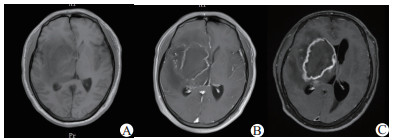

A:8月5日MRI增强:病变未强化;B:8月12日MRI增强:病变呈环形不均匀强化,局部脑膜可见线样强化;C:8月22日MRI增强:病变呈环形强化,范围较前扩大 图 1 患者入院后MRI增强影像结果

患者男性,39岁,以“发热头痛7 d,左侧肢体无力3 d,加重1 d”为主诉入院,7 d前受凉后出现发热体温最高40℃,伴头痛、咽痛、流涕,无寒战。3 d前出现左侧肢体麻木无力,无恶心、呕吐,头颅CT示右侧基底节区病变,脑梗死可能性大;查头颅MRI示右侧基底节区异常信号,考虑脑梗死并灶内渗血可能性大,颅脑MRA未见异常。血常规:白细胞18.43×109/L,血小板计数248×109/L;脑脊液检查:白细胞1 062×106/L,脑脊液蛋白1 765 mg/L, 在当地医院按“脑梗死/化脓性脑膜炎”给予对症治疗。1 d前患者左侧肢体无力较前加重,体温控制不佳,遂来我院。既往体健,无糖尿病等病史。入院查体:体温37.5℃,脉搏78次/min,呼吸18次/min,血压148/88 mmHg (1 mmHg=0.133 kPa),血氧饱和度99%,神志嗜睡状态,精神差,反应差,口唇无发绀,全身皮肤黏膜无黄染,浅表淋巴结不大,双侧瞳孔3.0 mm,等大等圆,对光反应灵敏,颈强直,颏下5横指,双肺呼吸音粗,未闻及干湿啰音,腹平软,腹壁反射正常,肌张力正常,左侧上下肢肌力均Ⅰ级,右侧肌力Ⅴ级,左侧躯干及肢体痛觉、触觉减退,右侧正常,左侧Babinski征阳性,右侧阴性;左侧克氏征阳性,右侧阴性。入院后查(2017-08-05)头颅MRI(图 1)示“右侧额颞叶、右侧侧脑室旁、右侧基底节、右侧大脑脚、脑桥右份占位病变,SWI提示含铁血黄素沉积,增强未强化”;行腰穿检查,脑脊液微黄,颅内压30 cmH2O(1 cmH2O=0.098 kPa),白细胞194 ×106/L,淋巴细胞70%,蛋白定量2 623.1 mg/L,糖3.4 mmol/L,氯化物128.4 mmol/L,抗酸染色阴性,墨汁染色阴性,腺苷脱氨酶8.65 ng/mL。诊断“颅内感染:化脓性脑膜炎?单纯疱疹病毒性脑炎?”,给予“美罗培南2.0 /8 h、更昔洛韦抗感染治疗”。2 d后行腰穿检查,脑脊液淡黄,颅内压27 cmH2O,白细胞550×106/L,淋巴细胞74%,蛋白定量1 798.9 mg/L,糖4.49 mmol/L,氯化物128.3 mmol/L;4 d后行结核分枝杆菌T细胞检测,抗原A 26(参考值0~5)、抗原B 13(参考值0~5);2017年8月12日行头颅MRI平扫+增强诊断(图 1)示“右侧额颞叶、右侧侧脑室旁、右侧基底节、右侧大脑脚、脑桥右份异常信号病变范围较前稍增大,病变呈环形不均匀强化、双侧额顶枕颞叶局部脑膜可见线样强化”,考虑“颅内感染:结核性脑膜炎”给予“异烟肼、利福霉素针、乙胺丁醇、吡嗪酰胺片、左氧氟沙星”抗结核治疗。2017年8月21日复查腰穿,脑脊液淡黄,颅内压40 cmH2O,白细胞78×106/L,淋巴细胞78%,蛋白定量2 446.1 mg/L,糖4.71 mmol/L,氯化物131.7 mmol/L。2017年8月22日行头颅MRI平扫+增强诊断(图 1)示“右侧额颞叶、右侧侧脑室旁、右侧基底节、右侧大脑脚、脑桥右份占位病变,边缘可见环形强化,范围较前增大,较大者病变范围56 mm×75 mm×49 mm(左右径×前后径×上下径)”。2017年8月23日神经外科行右侧颞叶基底节区脑脓肿穿刺抽吸术,术中抽出黏稠脓液约20 mL, 术后第2天患者曾出现意识障碍加重、瞳孔散大固定、呼吸急促,给予气管插管、呼吸机辅助通气、加强脱水及镇静镇痛减少应激反应降低颅内压等处理后患者神志逐渐恢复,脱呼吸机,拔除气管插管,术后病理提示“脓液真菌性炎症,形态符合毛霉菌(图 2),PAS染色阳性、六胺银染色阳性”,诊断考虑颅内毛霉菌感染,停用抗结核药物,给予“两性霉素B逐渐加量至75 mg/d, 单通路输注,输注时间10 h/d”,后转至上海华山医院感染科给予“两性霉素B联合泊沙康唑口服液治疗”,出院1年后随访患者仍服用泊沙康唑,一般情况较好,左侧上下肢肌力Ⅲ级,能在辅助下下床活动。

本文病例有以下临床特点:(1)中年男性、发病前有劳累、池塘游泳病史,池塘卫生情况差;(2)起病急、病程短,进展较迅速;(3)以发热、头痛、左侧肢体无力发病;(4)外周血白细胞计数及中性粒细胞比例明显增高,G试验阴性,GM试验阴性,脑脊液细胞数、蛋白较高,脑脊液结果提示颅内感染但不典型,明确何种颅内感染较困难,曾按照“单纯疱疹病毒性脑炎、化脓性脑膜炎、结核性脑膜炎”治疗,效果不佳;(5)影像学检查示,头颅MRI平扫加增强提示:右侧额颞叶、右侧侧脑室旁、右侧基底节、右侧大脑脚、脑桥右份病变伴出血,早期增强未强化,发病2周左右复查, 病灶呈环形强化,考虑脑脓肿可能性大;(6)外科手术,术中抽出20 mL黏稠脓液;(7)病理组织活检及染色确诊为毛霉菌感染;(8)患者因经济等原因应用两性霉素B治疗,后又加用泊沙康唑;体温恢复正常,脑脊液细胞数恢复正常,出院1年后随访患者恢复较好。